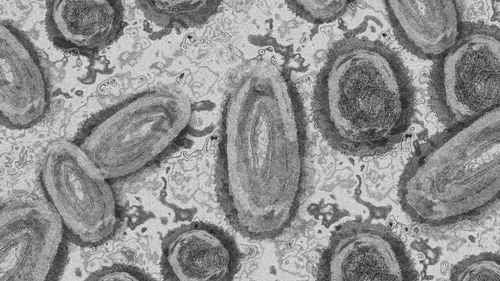

Variole du singe : 33 cas confirmés en France

Un premier cas a été identifié en Centre-Val de Loire.